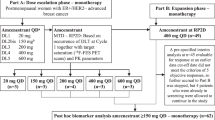

Based on this rationale, we conducted a phase II clinical trial combining the oral mTOR inhibitor everolimus with fulvestrant in patients with metastatic ER-positive breast cancer after AI failure. In addition to clinical assessment of treatment efficacy and toxicity, we collected tumor tissue where available and patients with accessible tumor were offered a research biopsy for future biomarker analysis.

Study design and agent administration

This was a single-institution phase II study of combined fulvestrant and everolimus after AI failure, starting therapy concomitantly on day 1 of enrollment. A core tumor biopsy was offered on study entry if disease was accessible (from primary tumor or skin) and preexisting tumor blocks were collected when available. Fulvestrant was administered intramuscularly (in the gluteus maximus) in a loading dose schedule as follows: 500 mg in two divided doses—one on each side on day 1, then 250 mg on day 14, and then 250 mg on day 28 and every 4 weeks ± 3 days thereafter. Everolimus was administered initially at a dose of 5 mg daily in the first 5-patient cohort for the first month of treatment and then increased to 10 mg PO daily after that. If two or more out of this initial cohort develop grade III toxicity or greater, then a second 5-patient cohort was planned to be recruited at the 5 mg daily dose level and the same toxicity rule followed. If treatment was tolerated based on this toxicity rule, then subsequent patients would start at 10 mg dose level. Since the frequency of grade-3 toxicity in the first 5-patient cohort was lower than that defined in the above rule, all subsequent patients received everolimus at the full starting dose level of 10 mg PO daily. Clinical evaluation for disease progression and tolerability of the regimen was evaluated every 2 weeks for the first two visits and every 4 weeks thereafter in outpatient clinic visits. In addition to routine chemistry and blood counts, fasting lipid profile and glucose were obtained every 2 months on study. After 2 months of enrollment, patients underwent their first formal radiologic disease assessment using RECIST criteria and imaging was done every 2 months thereafter and when indicated by symptoms suggestive of progressive disease (PD). Patients who experienced PD on protocol were taken off study and were required to have a safety follow-up 4 weeks after treatment discontinuation.

This was a single-stage phase II trial of the combination of fulvestrant and everolimus with a primary endpoint of time to progression (TTP) from enrollment. Secondary endpoints were the assessment of response rates per RECIST criteria, clinical benefit rate (CR+PR+SD of 24 weeks or more), toxicity assessment, and exploratory biomarker correlation with treatment benefit. A randomized trial of fulvestrant versus exemestane after non-steroidal AI failure in metastatic breast cancer (EFECT trial) served as the historical control for single-agent fulvestrant effect [5], with a reported median TTP on fulvestrant of 3.7 months. We hypothesized that median TTP in our trial will increase from 3.7 months for the historical fulvestrant-only control to 7.0 months on the combination of fulvestrant and everolimus in the current trial. A sample of 40 evaluable patients was calculated to show the increase in TTP with 80 % power and 5 % significance level based on a two-sided test of differences in survival times between historical controls and treated group. TTP was defined as time from study entry to disease progression or death, whichever occurs first. For patients without disease progression, the outcome was censored at the time of last assessment. Overall survival (OS) was defined as time from study entry until death or was censored at the time of last follow-up. Median TTP and OS were estimated using the Kaplan–Meier product limit survival curve. 95 % confidence intervals (CI) were provided for response and survival data. Wilcoxon signed-rank test was used to compare the median values of lipid profile parameters. Sample size calculations were conducted using NCSS (number cruncher statistical systems) software (www.ncss.com) and adverse events (AEs) were recorded using the NCI CTCAE v3.0 and were summarized by grade and overall frequency. Analyses were completed using SAS 9.3.

A total of 33 patients were enrolled on trial between March 2008 and October 2012; short of the planned accrual target, since FDA approval of everolimus for the same patient population in July 2012 lead to a significant drop in accrual. Of the 33 patients enrolled, two were ruled ineligible immediately after enrollment and were excluded from further analysis (one because of elevated creatinine outside the institutional reference range and one who required immediate palliative radiation to painful spine metastasis). Median patient age was 54 years with a range of 45–85 years (Table 1). All tumors were ER-positive and the majority were PgR-positive as well (84 %). Two patients had confirmed HER2-positive disease, one with de novo metastasis and the other one upon biopsy of metastatic disease in the liver at the time of relapse. The most common sites of metastasis were bone (84 %), liver (62 %), and lung (55 %), with 55 % of patients having 3 or more sites of metastatic disease (Table 1). Twenty-two patients (71 %) had received chemotherapy previously, 19 of them (61 %) in the adjuvant setting. Upon study entry, 74 % of the patients were receiving the AI as treatment for metastatic disease and 26 % as adjuvant therapy. Overall, patients were relatively heavily pretreated with 26 % receiving protocol treatment as their 4th-line endocrine therapy. Of particular note, 32 % of patients were classified as having AI-resistant disease (defined as relapse within the first 3 years of adjuvant AI or disease progression within 6 months of AI therapy for metastatic disease).

Efficacy analysis

Out of 31 evaluable patients, 29 (94 %) have discontinued therapy at the time of this report. Most common reasons for treatment discontinuation were disease progression (71 %), study-related toxicity (10 %), unrelated intercurrent illness (6 %), and patient choice (6 %), with 2 patients currently remaining on treatment (32 and 16 months, respectively). TTP is 7.4 months (95 % CI 1.9–12.1) (Fig. 1). The best response data using RECIST criteria are summarized in Table 2. The most frequent response observed was stable disease (42 %). There was one patient with liver-only metastatic disease who experienced complete response (CR) and remains on study treatment 32 months after enrollment. Partial response (PR) was observed in 3 patients (10 %) with an additional 2 patients with SD experiencing 26 and 28 % reduction in target disease measurement, respectively, just short of a PR. One patient (85 year old) who discontinued treatment in the first month because of grade-3 pneumonia and decline in her performance status experienced a dramatic disappearance of chest wall skin nodules and an 18 % reduction in her liver metastasis on imaging studies done one month after treatment. Overall, clinical benefit rate was 49 %. Interestingly, one-third of the patients exhibited de novo resistance to treatment as judged by first radiologic disease assessment at 8 weeks, and 2 additional patients experienced progression on the second disease assessment at 16 weeks. There were no discernible clinical variables that predicted duration of treatment benefit, but the majority of long-term responders were previously AI-sensitive as illustrated by individual patient treatment graph (Fig. 2).

Graph of individual patient duration of treatment with everolimus and fulvestrant in months. Patients with AI-sensitive disease are shown in blue and those with AI-resistant disease in red. The asterisks indicate patients who were censored at the indicated time points and the arrow indicates patients who continue on treatment at the time of this publication

At the time of this report, 22 patients have expired, none of them while on study treatment, with a median overall survival (OS) of 24.0 months (95 % CI 18.3–28.7) (Fig. 3).